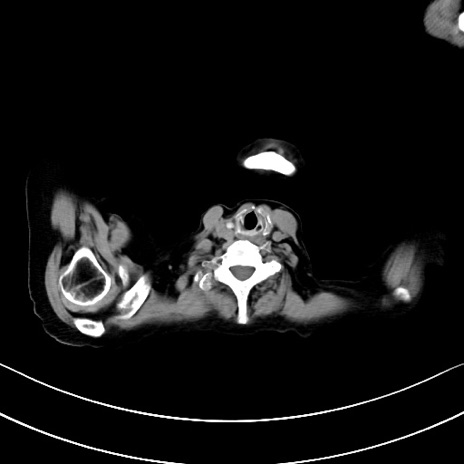

横断像

他院CT